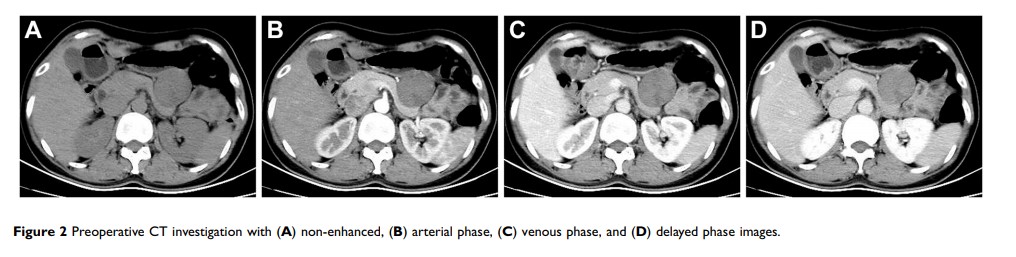

在超声和冷冻切片病理诊断中误诊的、起源于浆膜层的胃间质瘤:一份病例报告